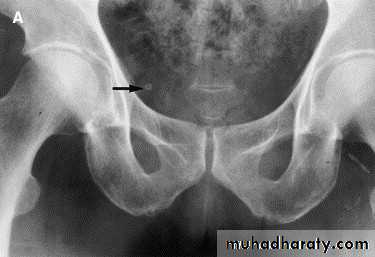

-Over 90% of calculi are radiopaque on plain films and virtually all on CT as very sensitive for detection of calculi, even those that appear radiolucent on plain film.

-Plain film may be useful in demonstrating calculi.

• Ddgx of stone on KUB :

• 1. Gall stone

• 2. calfied LN , cartilage ,fibroid,

• 3. Phlebolith: round, lucent centre.